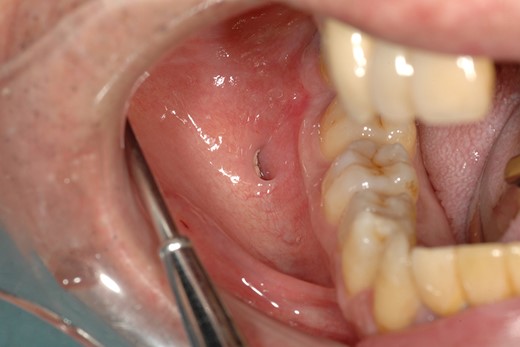

A 66-year-old man was referred to our institution in January 2018 for the diagnosis and treatment of a right buccal lesion. The lesion was first noticed approximately 1 month previously during an examination by his family dentist. The patient’s medical and family histories were unremarkable. He had no history of trauma to the face. Physical examination revealed bruising on the skin of his right cheek (Fig. 1). In the oral cavity, a mucosal outpouching (5-mm diameter, 10-mm depth) was observed in his right cheek. Food debris was seen in the outpouching (Fig. 2). The adjacent overlying oral mucosa was normal in appearance. The clinical diagnosis was a diverticulum-like lesion of the buccal mucosa. Excision of the outpouching was performed through an intraoral incision to stop food impaction (Fig. 3). It was easily separated from the surrounding soft tissues and completely excised (Fig. 4). The bottom of the outpouching was over the buccinator muscle on the lateral side. The buccinator muscle layer and oral mucosal layer were sutured separately. Histopathological examination revealed that the excised lesion was a true diverticular structure composed of a keratinising, squamous epithelial lining with a surrounding fibrous connective tissue wall, with inflammatory cell infiltration and haemorrhage (Fig. 5). In contrast to the normal buccal mucous epithelium, the diverticular epithelium had a thick stratum spinosum appearance with formation of anastomosed rete ridges (Fig. 6). The surface of the parakeratinised epithelium was corrugated. The histopathological diagnosis was a diverticulum of buccal region. The postoperative course was uneventful.

Intraoral photograph showing a pouch on the right buccal mucosa.